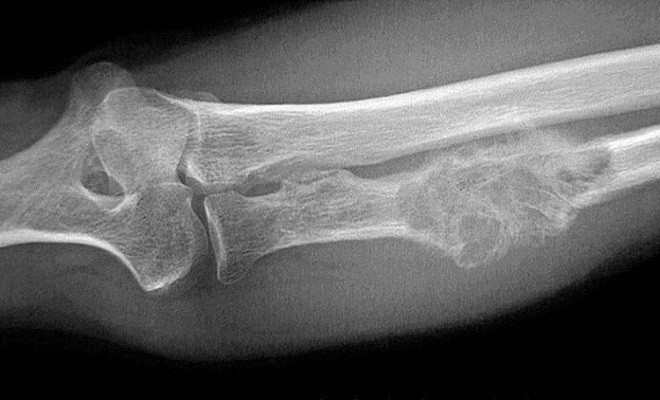

Según los autores del trabajo, los sarcomas o tumores localizados en el hueso son susceptibles de ser tratados con este método en el que se aplica el calor a las lesiones tumorales óseas por medio de agua a 45 grados centígrados o vapor de agua para propiciar la muerte de las células neoplásicas.